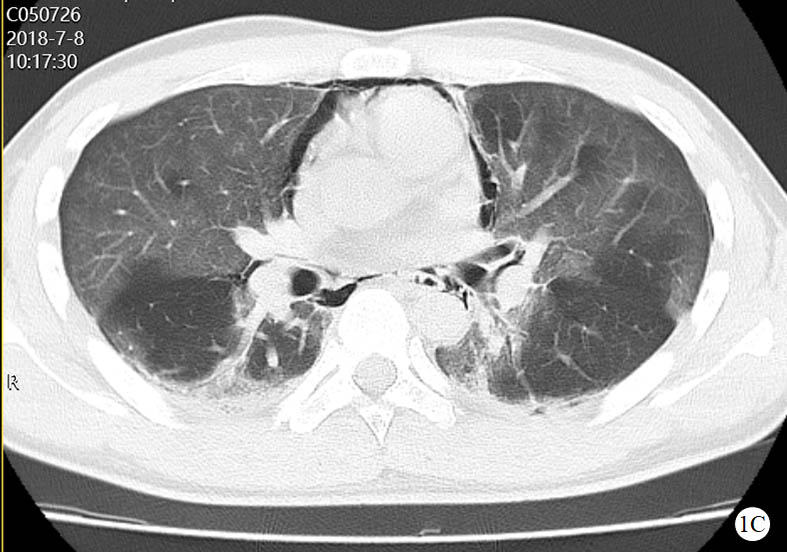

图 1 患者口服百草枯后胸部CT影像学变化

2018-07-08 CT图